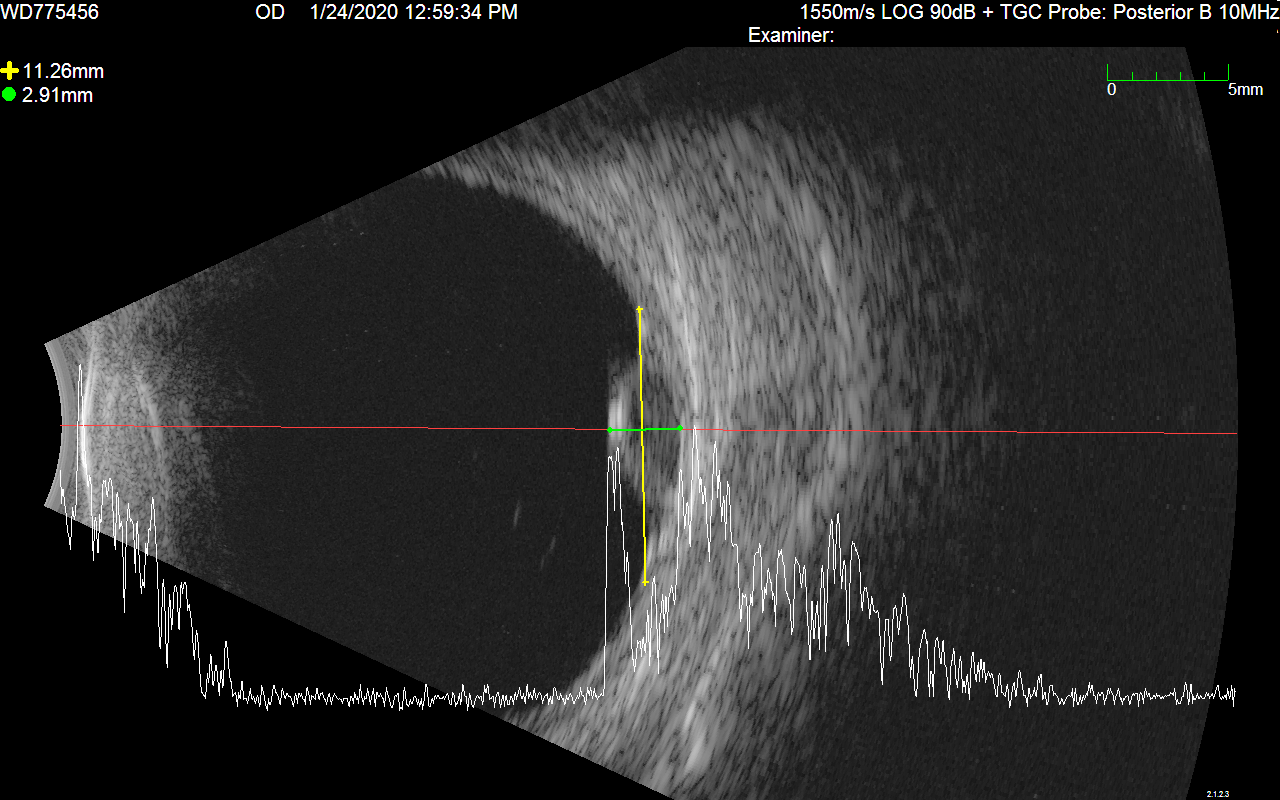

Ultrasound Images

A pair of ultrasound b-scans are used to determine the elevation of the tumor. Ideally, these images should illustrate cross-sections of the longest dimension of the tumor, and a plane perpendicular to that longest dimension. Radial and circumferential cross-sections are also acceptable. Eye tumors are often not clearly visible in CT (or MR) imaging alone. Ultrasound b-scans provided the most accurate measurements and cross-sections of ocular tumors for treatment planning purposes.

US1

US2